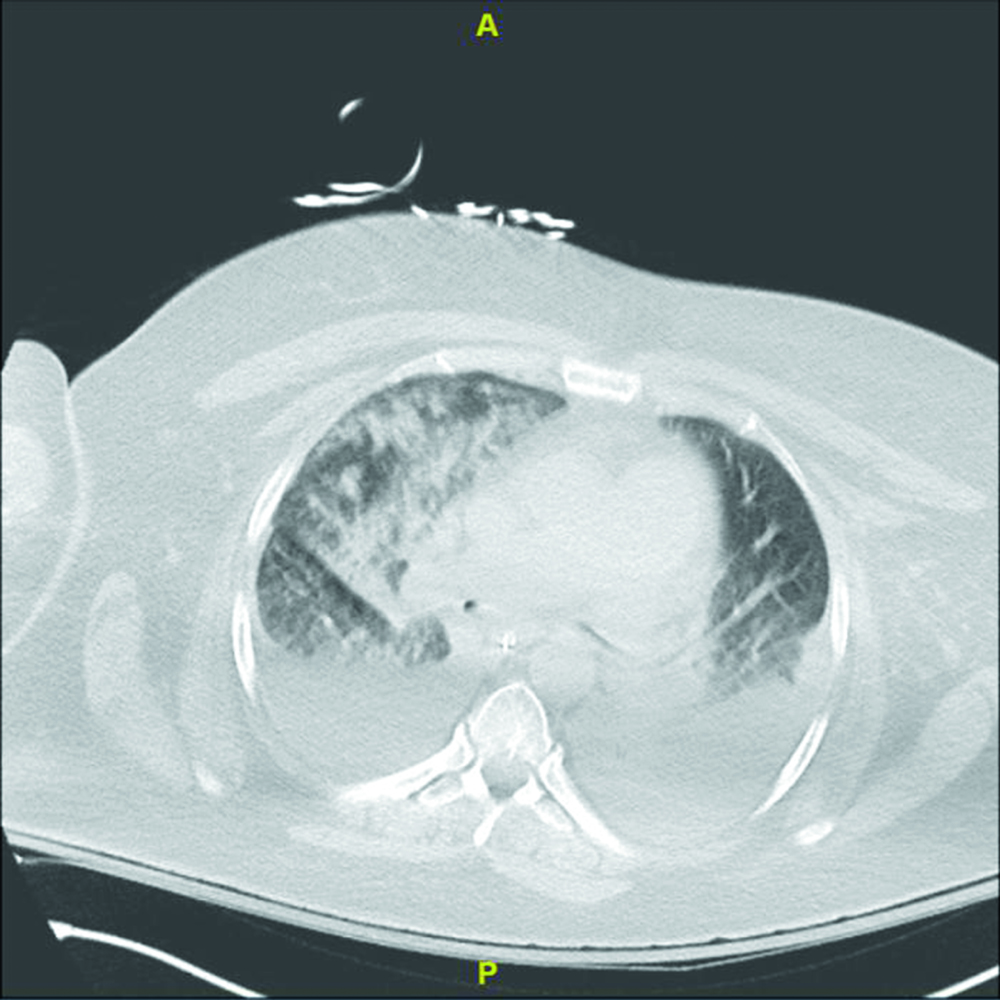

Blood work on admission showed white cell count 8200 cells/µL, hemoglobin 11gm/dL, platelets 193000/µL, and procalcitonin 0.730 ng/mL; her prothrombin time was 12.3 seconds (INR = 1.18). During the first three days of admission, her hemoglobin count dropped to 8.8 gm/dL. She had no sign of active bleeding. Her electrocardiogram showed a sinus rhythm and incomplete right bundle branch block with non-specific ST-T wave changes in anterior leads. Chest x-ray on admission showed extensive opacity in the right lung and a dense opacity in the left lung base. The next day the chest x-ray had worsened with bilateral opacities (Figure 1). Chest computed tomography scan showed bilateral pleural effusions with bilateral pulmonary infiltrates (Figure 2). The patient was initially placed on empiric antibiotics for hospital-acquired pneumonia; however, no clinical improvement was noted over 48 hours, and antibiotics were discontinued.

Figure 2

Figure 2. Computed tomography of the chest reveals bilateral pleural effusions and infiltrates, especially in the right lung.